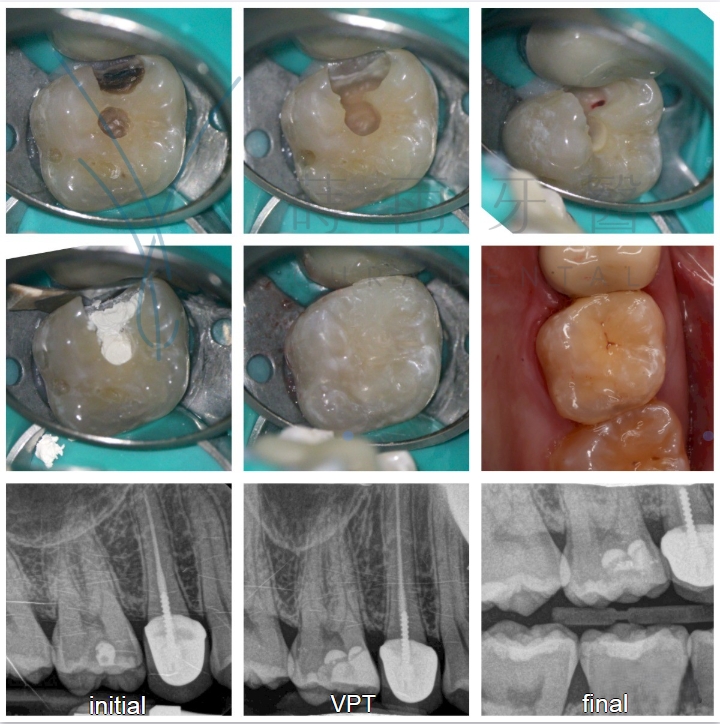

案例分享

拯救牙齒 避免根管治療 – 活髓保存術

過去一旦牙髓腔暴露於口腔環境中,為了避免無法預知的感染後患,往往只能進行根管治療(抽神經),將牙髓腔內所有組織斬草除根,以免細菌死灰復燃,但牙髓腔內的組織是供應養分的主要來源,也是牙齒接受冷熱、痛覺的末梢神經,肩負牙齒知覺的重要功能,在牙髓腔組織尚未全然受到細菌感染的狀況下,經醫師評估,若牙髓腔尚有健康牙髓,在清除感染組織後可以選擇做活髓保存術。